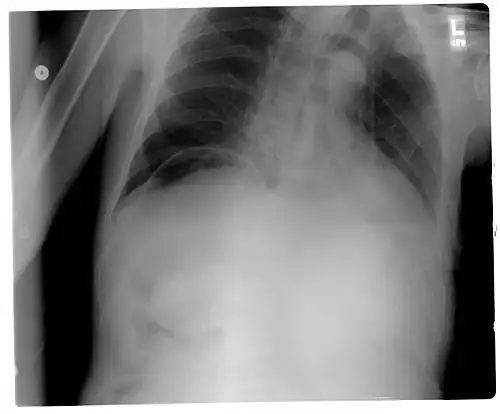

Frontal chest X-ray. The air bubble below the right hemidiaphragm (on the left of the image) is a pneumoperitoneum.

As differential diagnoses, a subphrenic abscess, bowel interposed between diaphragm and liver (Chilaiditi syndrome), and linear atelectasis at the base of the lungs can simulate free air under the diaphragm on a chest X-ray.